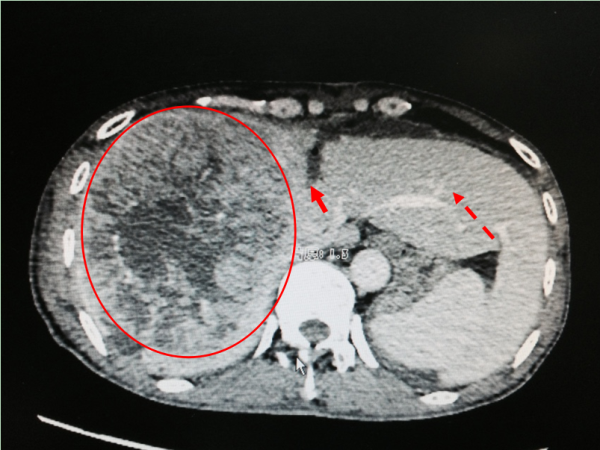

• 男子二十余年不患病 一病便是巨大肝癌——我院第二例二步肝癌切除术(ALPPS术)成功完成

男子二十余年不患病 一病便是巨大肝癌——我院第二例二...

突然接到电话说我哥住院了,觉得非常不可思议!十多天后,粱先生的小弟还对哥哥突然生病一事很疑惑。 因二十几年没有生过病,突然就住院了,...